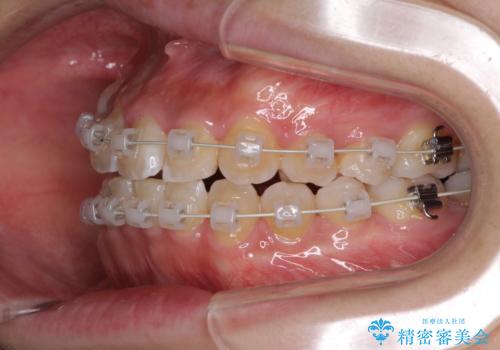

- 矯正装置

- 審美装置

- 2年10ヶ月

- 前歯のでこぼこと乳歯が残るほどの八重歯を気にして来院された患者様です。

非抜歯にてワイヤー矯正にて治療することとしました。(ただし、親知らずと乳歯は抜歯)

犬歯は歯根が太く長いため、移動には時間を要します。しかし、犬歯は機能面から考えて残すことを選択したいため、長期間をかけて治療を行うこととしました。

治療の度に歯列が改善していったため、長期間の治療も楽しく過ごしていいただき、満足のいく仕上がりとなりました。